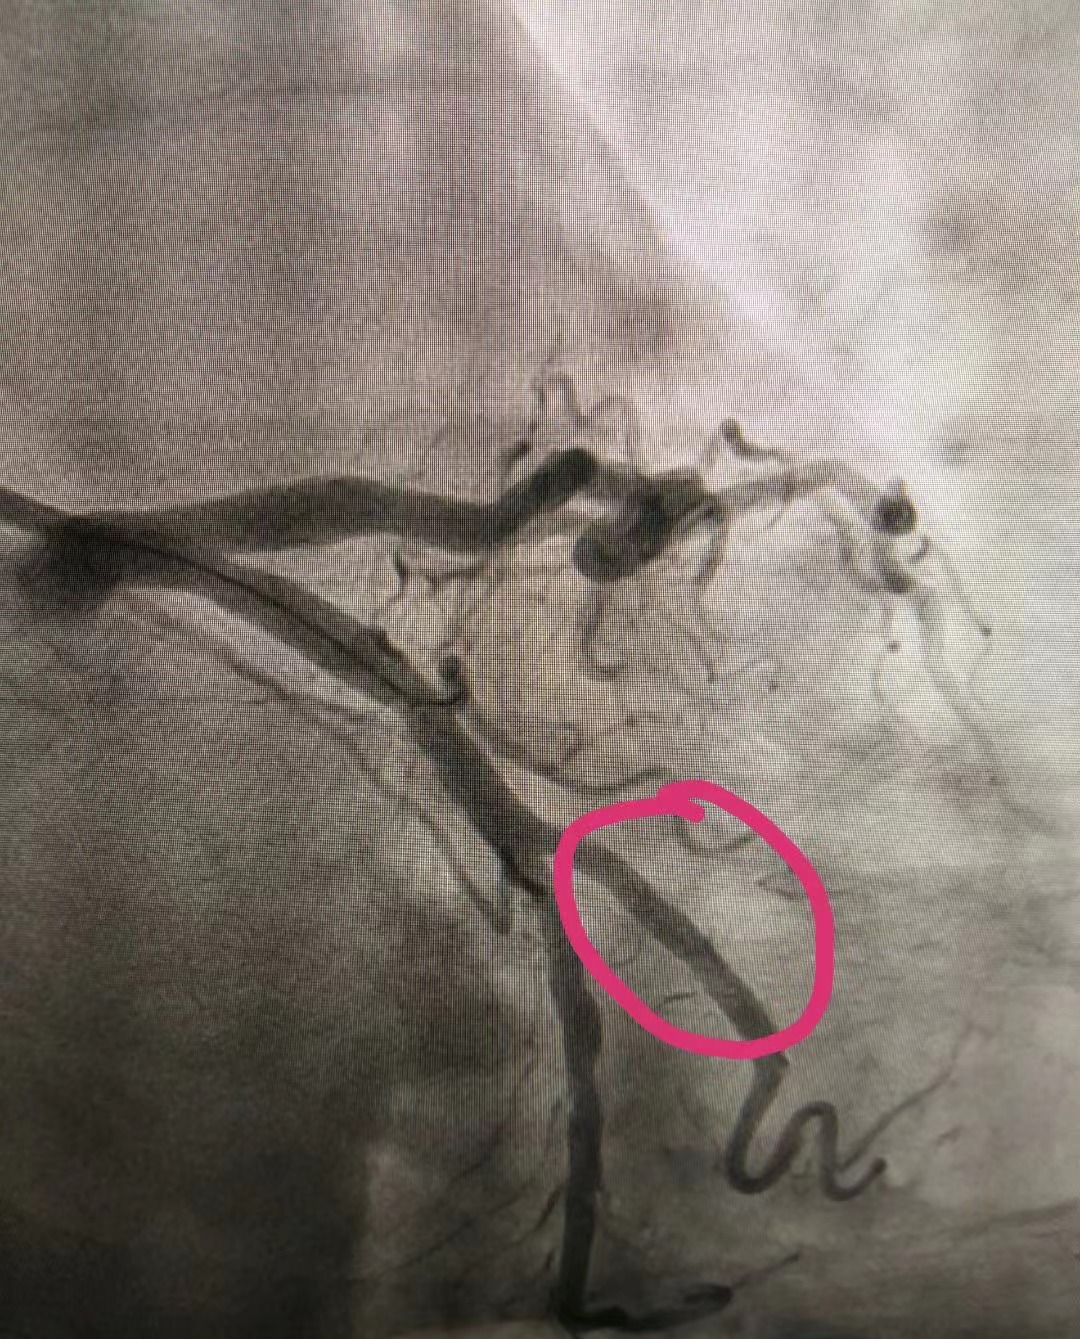

PCI术后

12月18日,70岁的杜大娘因“阵发性胸闷、心悸3天”于门诊急入住心内二科,成为科室成立当天首位住院患者。副主任王涛迅速接诊,为其查体,询问病史,患者心电图示:窦性心律、频发房早。科主任李永平凭借多年临床经验,考虑为急性冠脉综合征,不稳定性心绞痛。情况紧急,李主任与王主任共同评估患者病情后,立即向家属说明病情,并及时联系介入室,进行冠脉造影检查,发现老人回旋支OM2近段80%-90%×8mm狭窄,前向血流TIMI3级,符合PCI(即:经皮冠状动脉介入治疗手术)治疗指征。时间就是生命,在医护人员的缜密配合下,为患者行PCI治疗,并置入支架1枚。患者术中无任何不适,精神状态良好,术后安返病房。住院期间,护理人员严格执行护理核心制度,做好危重冠心病患者的护理工作。为表感激之情,患者家属特意到办公室对心内二科医护人员进行感谢。